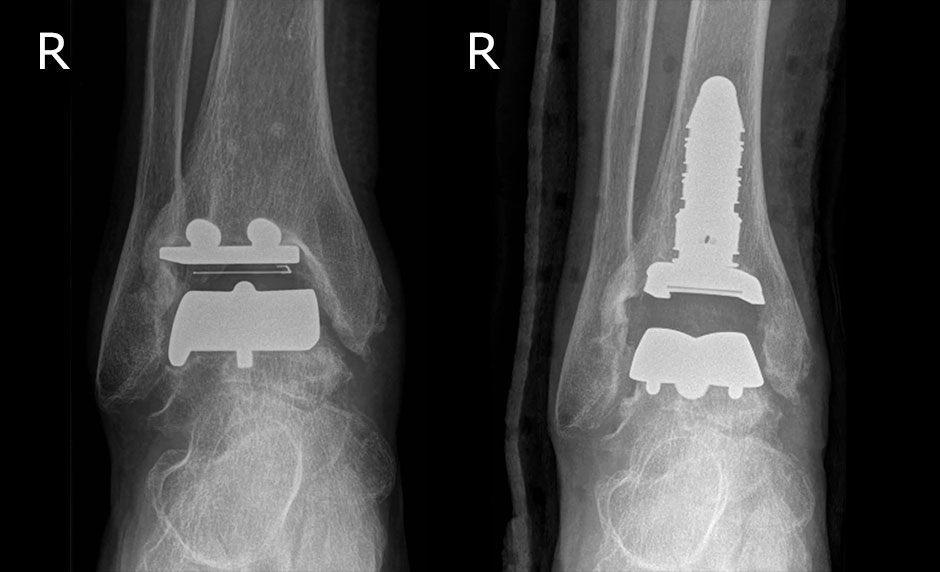

M.B., w., 57 Jahre, gelockerte und fehlpositionierte STAR OSG TEP, jetzt gewechselt auf das modulare Inbone System Fa. Stryker. Die Patientin befindet sich schmerzfrei mit zeitgerechter Funktion in der Rehabilitation.